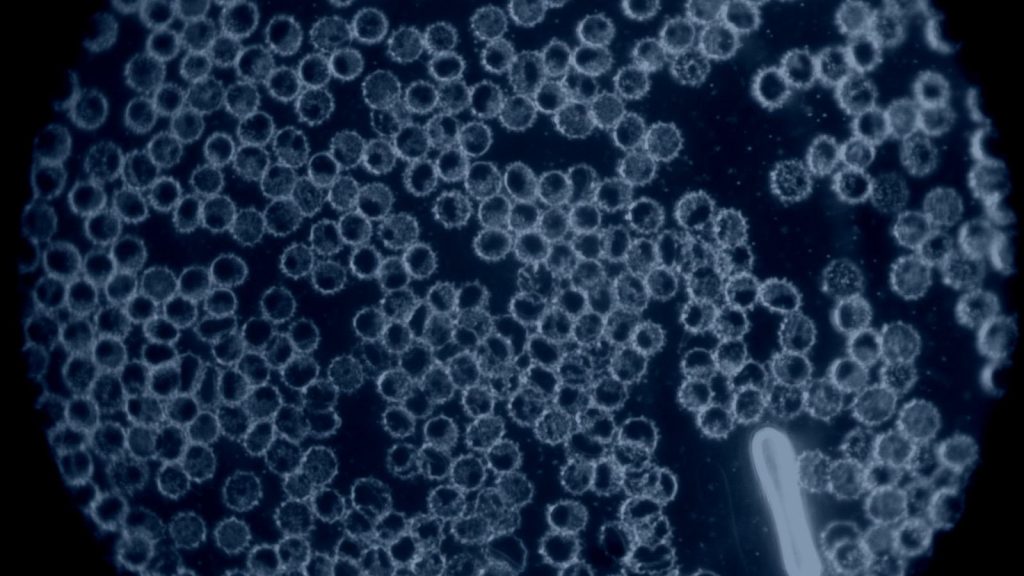

Foto: UV-Licht Mikroskop

Blutbild voll Spikes nach diversen Covidinfektionen und 3x geimpft

Aufgenommen August 2025

Während und nach einer Behandlung mit herkömmlichen Methoden

(Sauerstoff, Nährstoffe, Blutaustausch)

Foto: UV-Licht Mikroskop

Blutbild nach 6 Wochen Behandlung mit Sauerstoff und Nährstoffen

Es sind einzelne Blutzellen erkennbar, es sind allerdings auch weiterhin Spikes im Blut

Aufgenommen Ende Sept. 2025

- Weniger Spikes im Blut

- Einige klar abgesetzte Blutkörperchen

- Keine nachhaltige 100% Ausleitung der Spikes (lineare Tromben)

- Besserung der Sauerstoff / Energieversorgung des Körpers

- Weiterhin zu wenig Sauerstoff im Blut für ein aktives Leben